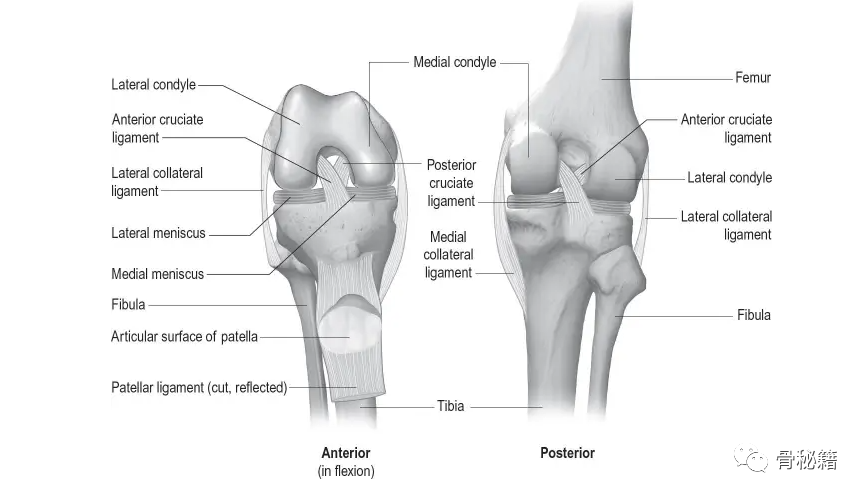

二、韧带

膝关节韧带经过专门设计,可适应广泛的运动和灵活性,同时为负重提供必要的稳定性。

• 内侧副韧带。

• 侧副韧带。

• 前交叉韧带。

• 后交叉韧带。

三、半月板

是新月形的纤维软骨结构,外围位于内侧和外侧胫股隔室。这些结构参与负重过程并增强膝关节的稳定性。